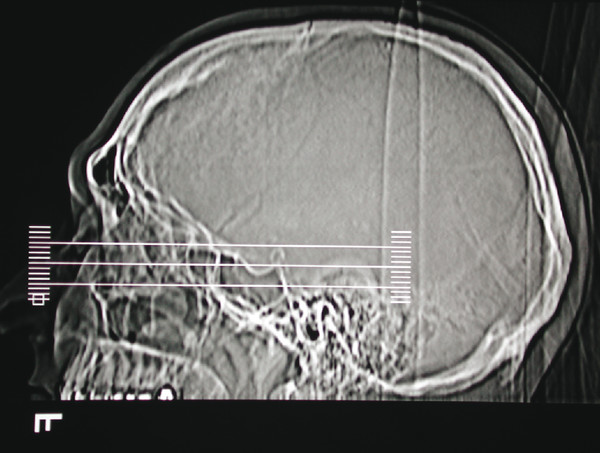

For optic nerve tumors and orbital apex lesions, both CT and MRI may provide complementary information (Fig. 18‑11).

An MRI image is generated based on the movement of protons in tissues when a patient is placed into the magnetic field of a scanner and then subjected to a series of radiowave pulses. The radiowave pulses are varied by the radiologist to generate T1- and T2-weighted scans. A T1-weighted scan is recognizable by the dark appearance of the vitreous in contrast to the very bright appearance of the vitreous on a T2-weighted scan (Fig. 18‑12). T1-weighted scans provide the best anatomical detail. Fluid creates a bright signal on T2-weighted scans. A “fluid void” is seen in areas of high vascular flow where the protons are moving too rapidly to be imaged. Cortical bone appears as a dark area on MRI, because the protons are too tightly bound to generate a signal.

The scout film should be examined. This shows the slices as sectioned by the computer (Fig. 18‑13), which assists in orientation of the plane of scanning performed. The images should be examined systematically, comparing both sides for any asymmetry. It is important to look for any rotation of the head that can lead to misleading asymmetries of no diagnostic significance. The bone structures are examined first, followed by the soft tissues. Interpretation of the images requires practice and experience. It is extremely helpful to review the images with an experienced radiologist, preferably in a multidisciplinary team meeting.